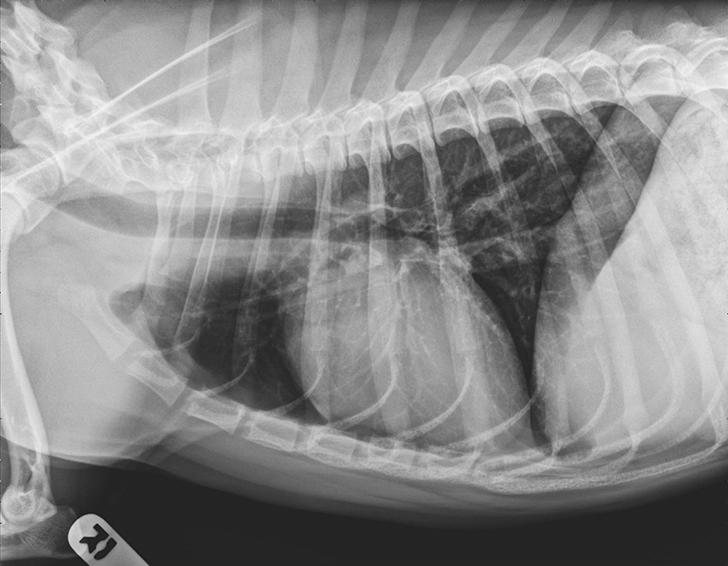

EBP Causing Chronic Coughing in a Dog Clinician's Brief Epistaxis Dog Clinician's Brief A careful, thorough physical examination is essential to prioritize the diagnostic differentials in dogs and cats. Most acute or sudden nosebleeds are caused by simple trauma or by upper respiratory. The dog is an indoor pet that only goes outside. Following are differential diagnoses, listed in order of likeliness, for patients presented with epistaxis. Fortunately, despite the owner’s impression, the. Epistaxis Dog Clinician's Brief.